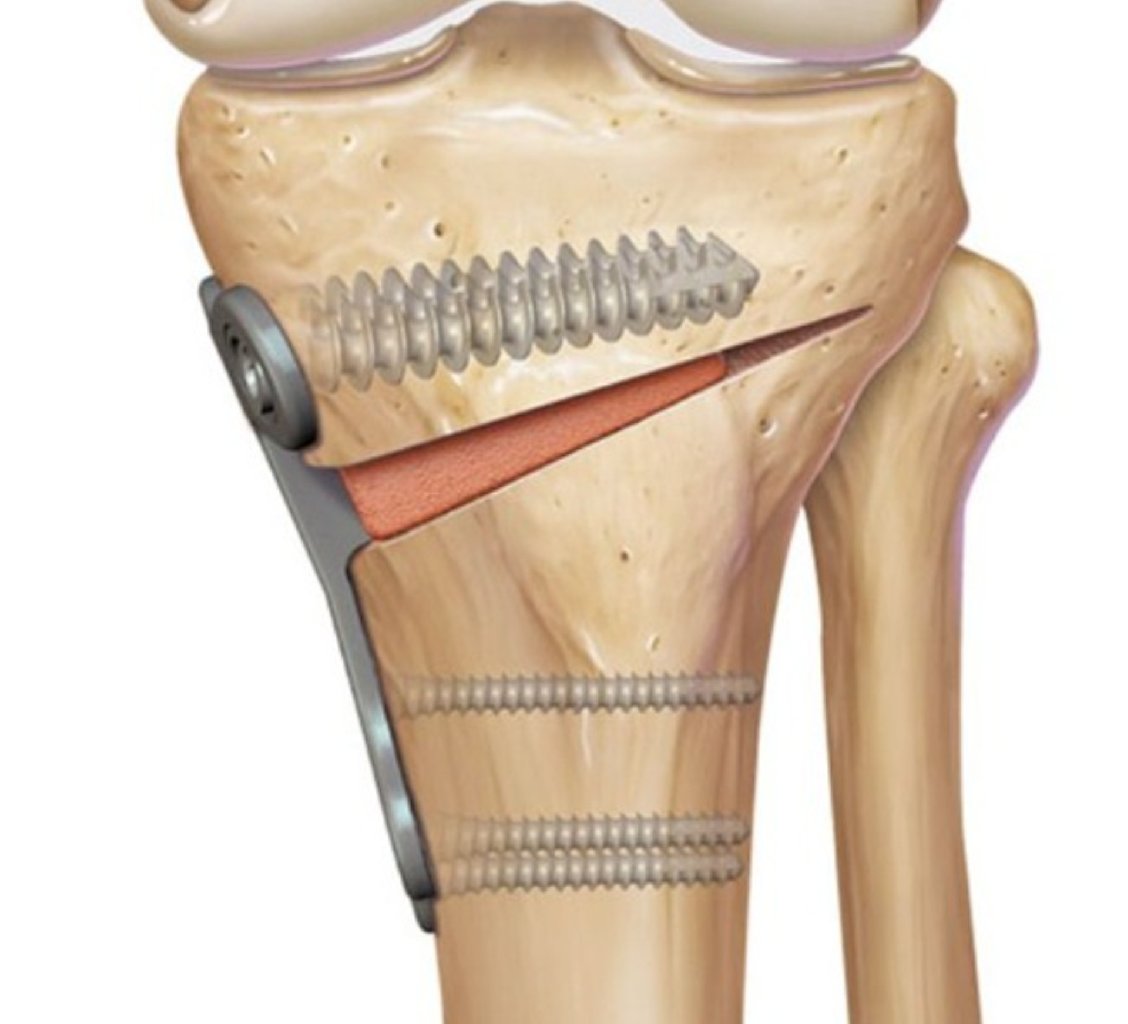

Diz Osteotomiyası: Diz əyilməsi kimi problemlərin düzəldilməsi üçün istifadə olunur. Məsələn, diz os ...